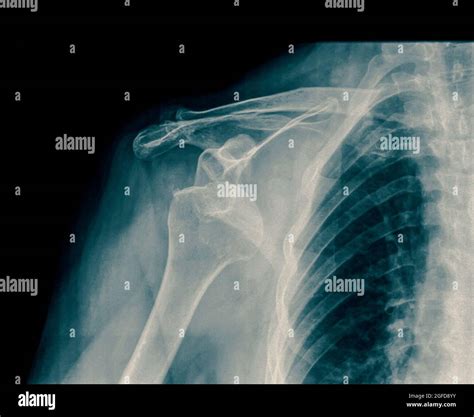

Experiencing a sudden, sharp pain in your shoulder after a fall or a sports-related impact is a distressing ordeal. Often, the first thing medical professionals will order to assess the situation is a Dislocated Shoulder X Ray. Understanding why this imaging is critical, what it reveals, and how it guides your recovery journey is essential for anyone dealing with this common orthopedic injury. A dislocated shoulder occurs when the ball of your upper arm bone (the humerus) pops out of the shoulder socket (the glenoid). Because this area is complex, precise imaging is the gold standard for confirming the diagnosis and ruling out associated complications.

• Detecting fractures: Intense trauma can break the humerus, the glenoid rim, or the acromion. These fractures change the treatment plan significantly.

Hill-Sachs Lesion A small indentation or "dent" on the back of the humeral head, often caused by the bone hitting the rim of the socket during dislocation.

Bankart Lesion A tear or fracture of the labrum (cartilage) at the front of the glenoid socket.

Greater Tuberosity Fracture A small break in the bone where tendons attach, commonly seen in elderly patients with shoulder dislocations.

Following the confirmation provided by the Dislocated Shoulder X Ray, the medical team will proceed with reduction. Once the shoulder is back in its proper position, the doctor will often order a post-reduction X-ray. This second round of imaging is vital to confirm that the bone is correctly seated and that no new fractures were created during the reduction procedure.